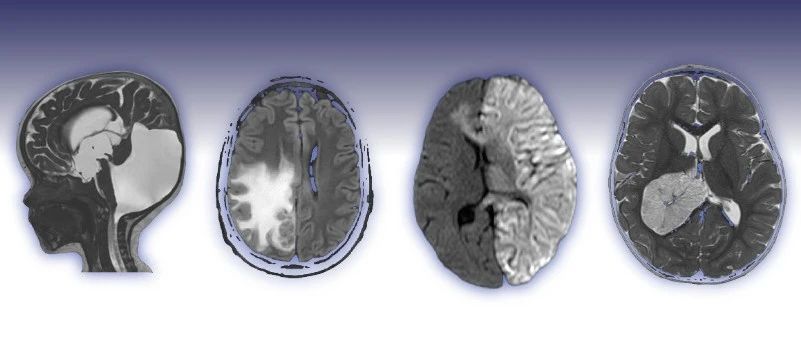

弥漫性大B细胞淋巴瘤!

医学影像  yxyx-app  医学影像APP,打造伴随医生快速成长的影像学习社区。与影像园(Xctmr.com)一起提供最全面的影像案例库、基础(解剖、病理、影像诊断)知识、影像技术及考题等,为医生提供最佳的医学影像参考。【所属科室】神经外科【基本资料】患者,男,53岁【主诉】进行性头晕、走路不稳伴间断呕吐1个月,视物成双1周【专科检查】双眼视力粗测正常,水平眼震,双瞳孔等大正圆,光反射灵敏,左眼外展受限。左侧面部(V1,2,3)感觉减退,左耳听力粗测下降,左侧味觉减退,伸舌居中。双侧腹壁反射消失、右侧提睾反射消失、左侧提睾反射减弱。四肢肌力5级,左侧肢体共济运动障碍。双侧病理征阴性。...